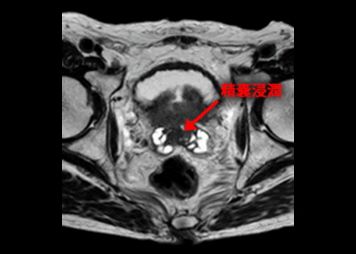

前立腺がんの前立腺外浸潤、精嚢浸潤の評価にMRIは有用です。

Gleasonスコア:5+3

TNM分類:T4N1M1

T2強調画像により精嚢浸潤が認められます。

T2強調画像